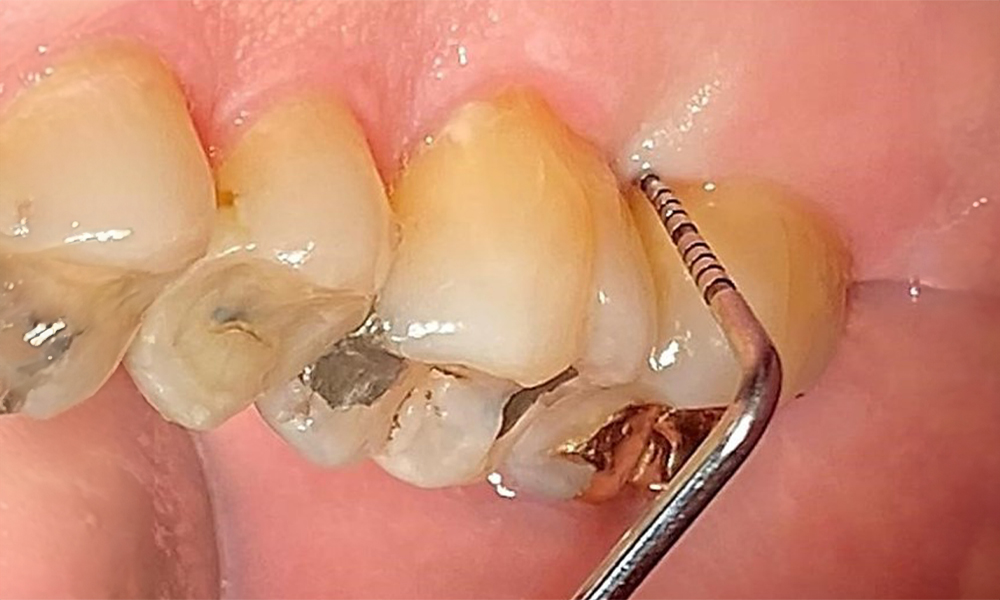

Пациентът има пълно съзъбие с 28 зъба, което включва амалгамни и композитни пломби в областта на моларите и премоларите. На зъб 14 има видима клинична маргинална празнина. Зъб 27 има адекватна златна инкрустация. Налице са и генерализирани атриции и абразии. (фиг. 2, фиг. 3, фиг. 4, фиг. 5, фиг. 6)

Пациентът е с пародонтит II стадий, степен В (5). Клиничните дълбочини на сондиране от 1 до 3 mm са във физиологичния диапазон. Локализирани дълбочини на сондиране от 5 mm са наблюдавани медиопалатинално на 17 и 27. Налице са генерализирани рецесии от 1 до 3 mm с частична загуба на интердентални папили (фиг. 2, фиг. 3, фиг. 4)